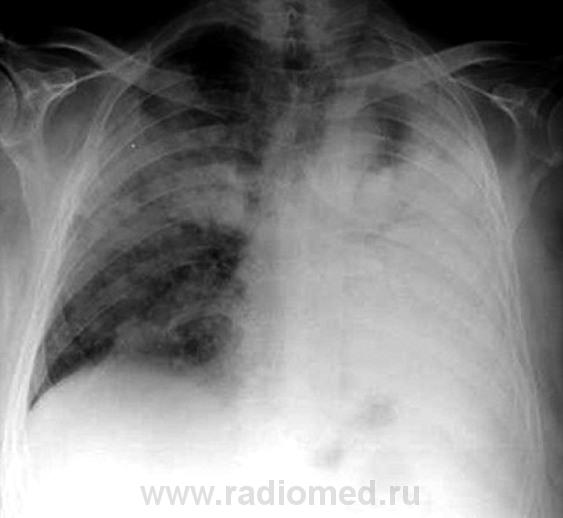

В УБ была произведена рентгенограмма в прямой стандартной проекции. Боковую не делали...

Жаль, что нет боковых снимков. На прямых не вижу молочных желез. Онкология с поражением обоих легких и ателектазом левого легкого. Насчет жидкости точно не скажу, но сердце смещено влево...

Терапевты по клинике выставляли двустороннюю пневмонию, но как-то не все укладывалось а данную нозологию. А, по рентгенограмме, слева, увидев "воздушную" бронхограмму, так и рентгенолога уговорили по поводу "пневмонии".

Нет, терапеты в УБ, выставили "пневмонию", рентгенолаборант сделал снимок. Рентгенолог, который приезжает "описывать снимки" колебался между пневмонией и бронхиолоальвеолярным раком, настаивая на дообследовании. Вот пациента, прямиком и отвезли на КТ, родственники натояли.

koriatus, неужели Вы не видите стрикулы, так характерные для онкологии? Инфильтрации как таковой нет. Почему ателектаз верхней доли, как раз слева на верхушке прослеживается легочная ткань? А ателектаз только дополняет картину, и настраивает в первую очередь на онкологию.